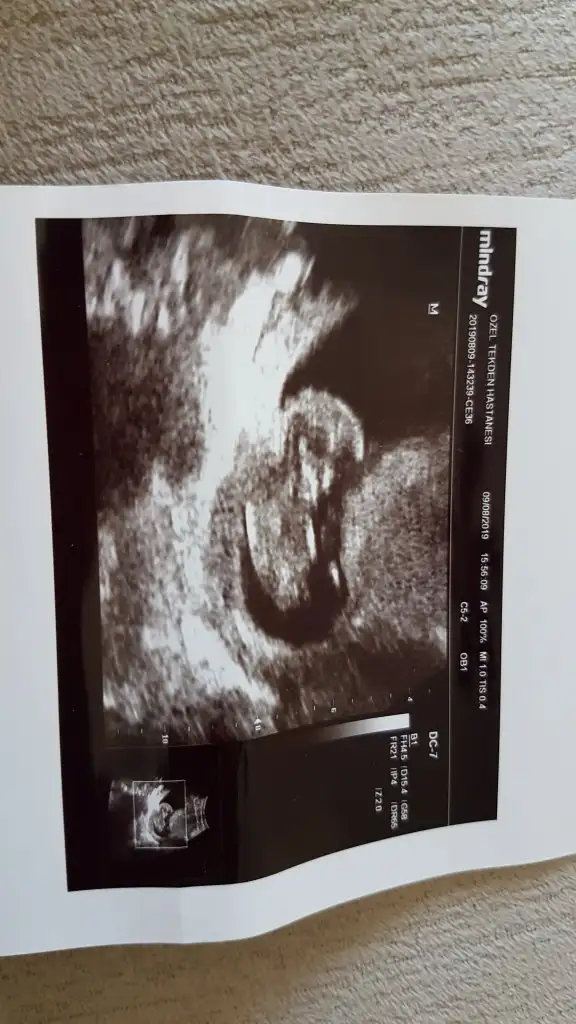

sizce kız mı erkek mi tahminde bulunabilen..

bu 12 haftalıkken